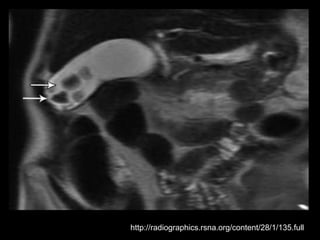

Duplicação da Vesícula Biliar

Ocorre em 0,025% da população;

Causada pela revacuolização incompleta da

vesícula biliar primitiva, que resulta na

persistência de um septo longitudinal.

A cavidade de cada vesícula precisa ter seu próprio

ducto cístico.

A maioria dos casos de duplicação relatados inclui

um quadro de colecistite com cálculos.

Várias condições podem simular vesícula

duplicada.

Exemplos: VB dobrada, VB bilobada, cisto de

colédoco, líquido perivesicular, divertículo da VB,

VB atravessada por feixe vascular e

adenomiomatose focal;

Complicações: torção, papiloma, carcinoma,

obstrução do ducto comum e cirrose biliar;

Foram relatadas vesículas triplas e quádruplas!!!